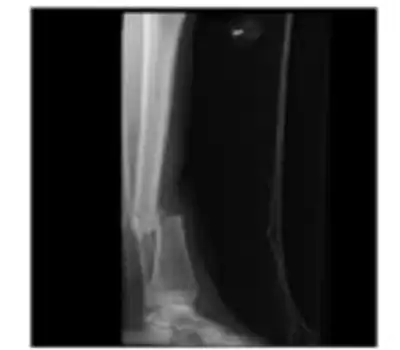

Tibia shaft fracture

| Open fracture of the shaft of the tibia. | |

Tibia shaft fracture is a fracture of the proximal (upper) third of the tibia (lower leg bone). Due to the location of the tibia, it is frequently injured. Thus it is the most commonly fractured long bone in the body.[1]

Patients with tibial shaft fractures present with pain and localized swelling.[2] Due to the pain they are unable to bear weight. There may be deformity, angulation, or malroation of the leg.[2] Fractures that are open (bone exposed or breaking the skin) are common.